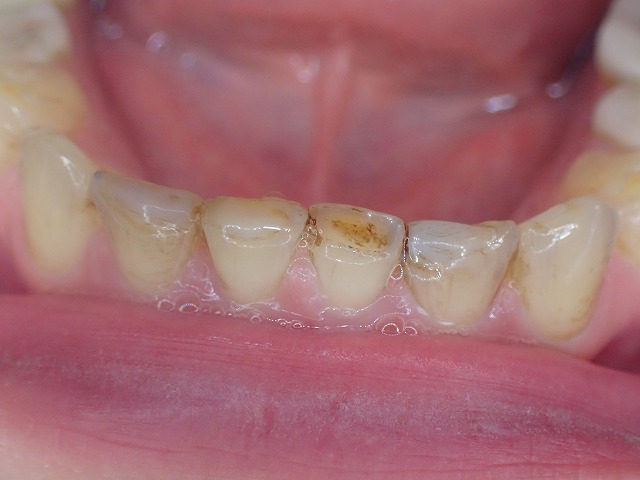

下顎の前歯にレジン充填

このWEBでも再三指摘していることですが

歯ぎしりですり減った前歯の先端に

レジン充填をすると減りが加速します。

矯正のマウスピースをしているので

減りは少ないのですが、マウスピースなしでは

あっという間に吹き飛ぶリスクがあります。

下顎前歯の先端は歯ぎしりで大きく摩耗している

●歯の長さ40%が失われている

●先端がレジン充填されている–やらないほうがいい治療

●レジン充填で歯の切端を充填すると、

咬合圧力で吹き飛ぶリスクが高い

(この症例ではリテイナーが入っているので先端は割れにくい)